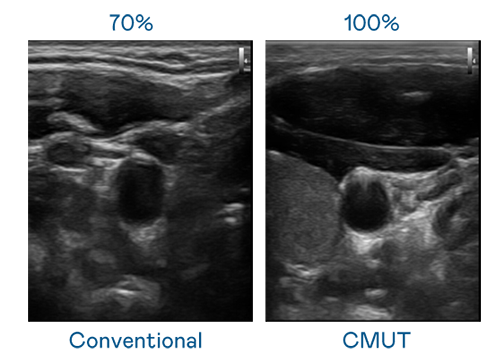

CMUT 技术是一种用电容式微机电元件来产生超音波讯号的技术。与传统 PZT 压电式技术相比,CMUT 频宽增加 30%,更宽频的超音波讯号让影像解析度大幅提升,是实现高影像品质医疗超音波扫描、促进精准医疗发展的关键技术。

大频宽带来超清晰影像

超音波影像的解析度高低,首先取决于探头能发出的讯号频宽。果冻九一麻花 CMUT 可提供高清晰的超音波讯号,提供高频宽、高灵敏度、影像纹理细节更高的超音波影像,协助医护人员缩短影像判读时间及利用精准的医疗影像进行诊断。